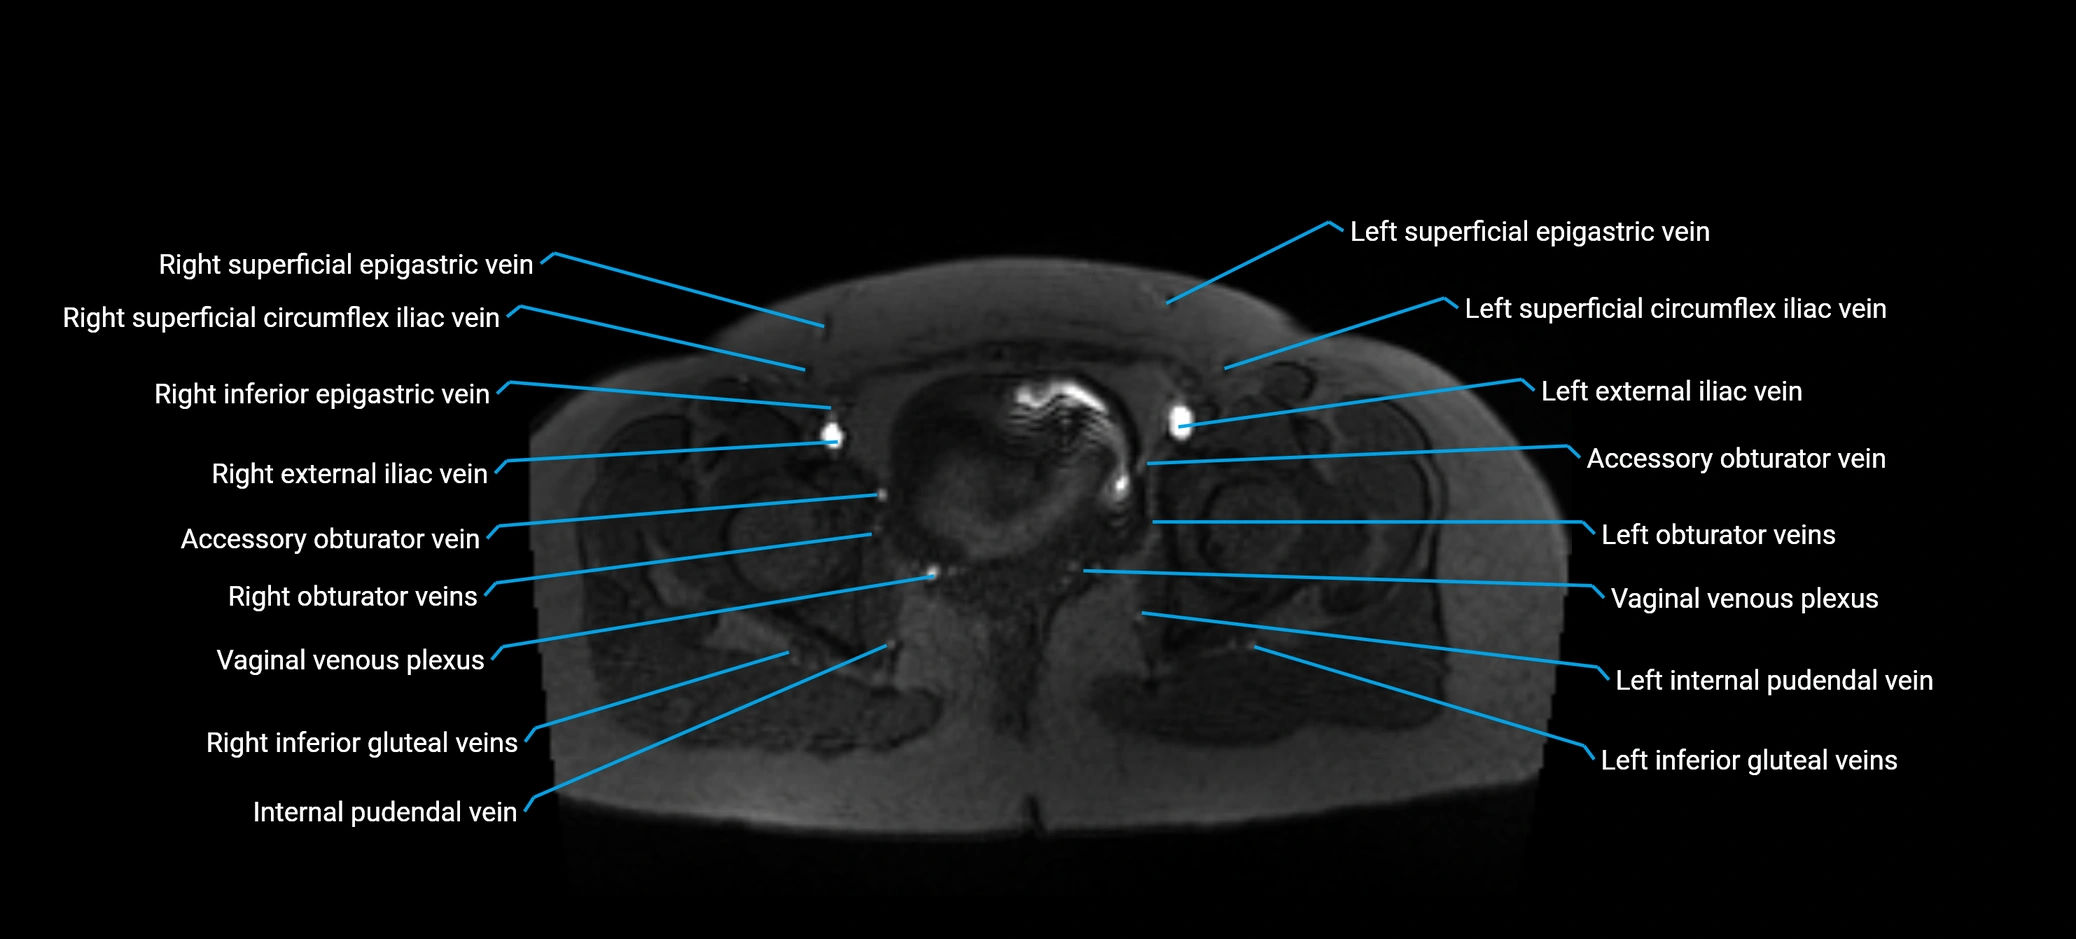

MRI image

image